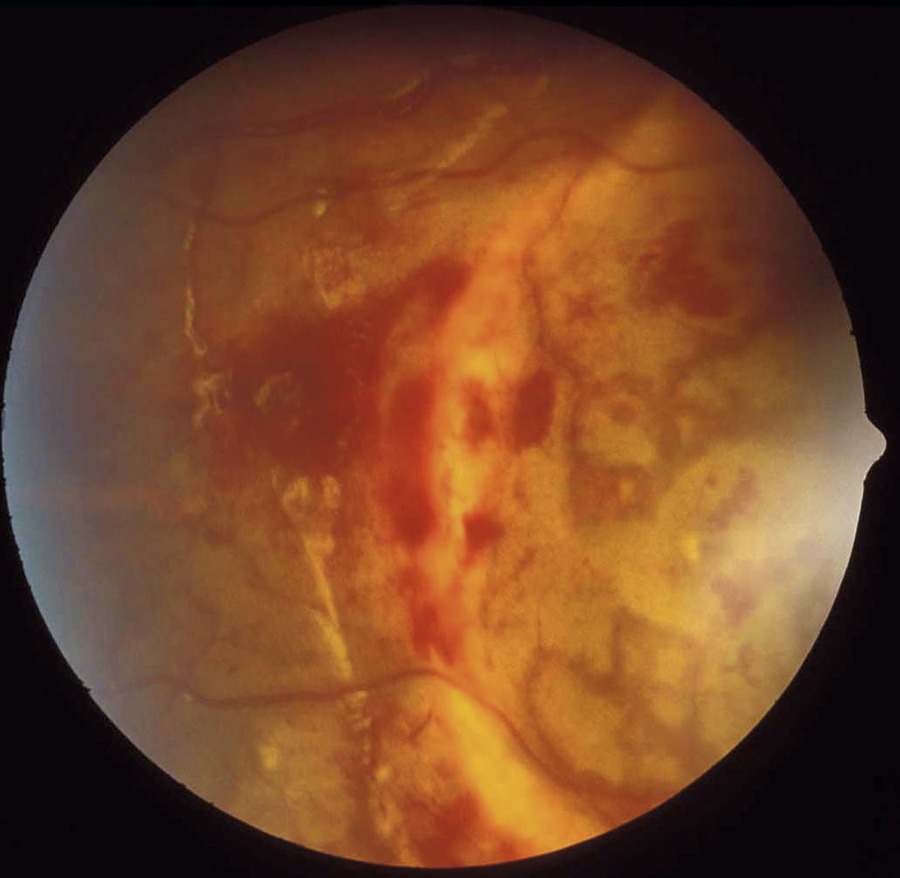

Figur 1. Talrika och utbredda intraretinala ögonbottenblödningar, s k punktblödningar, som sträcker sig ända ut till näthinnans periferi, dvs till ora serrata, hos barn som utsatts för AHT. Blödningarna är talrika, dvs för många för att räkna. Figur 1–4: Med tillstånd från Alex V Levin, MD, MHSc, Wills Eye Hospital, Philadelphia.